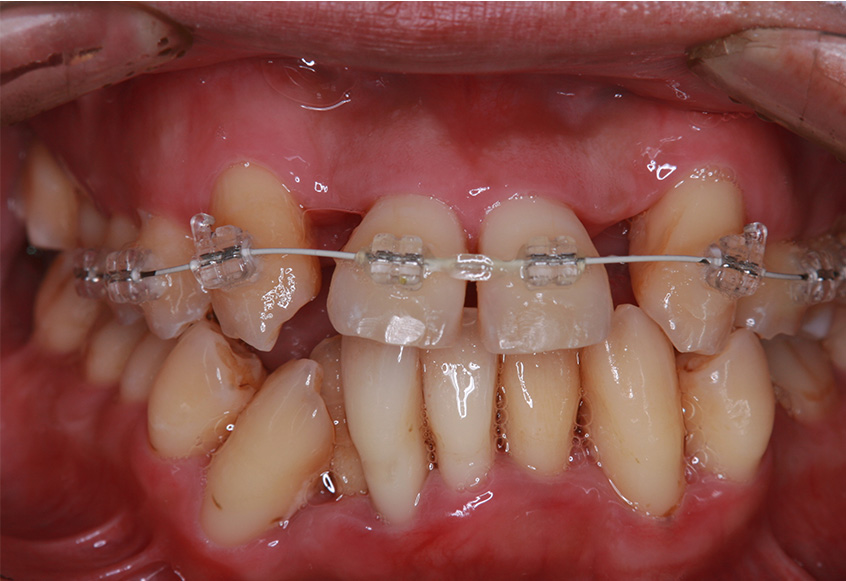

治療開始後3ヵ月経過すると、前歯の隙間や全体の乱れが減ってきました。口笛が吹けるようになったとのことです。

最初のお口の中 治療開始3ヵ月後

6ヵ月経過すると、矯正治療を終了し、前歯に被せ物の治療を行いました。

最初のお口の中 2025/3/22

被せ物装着